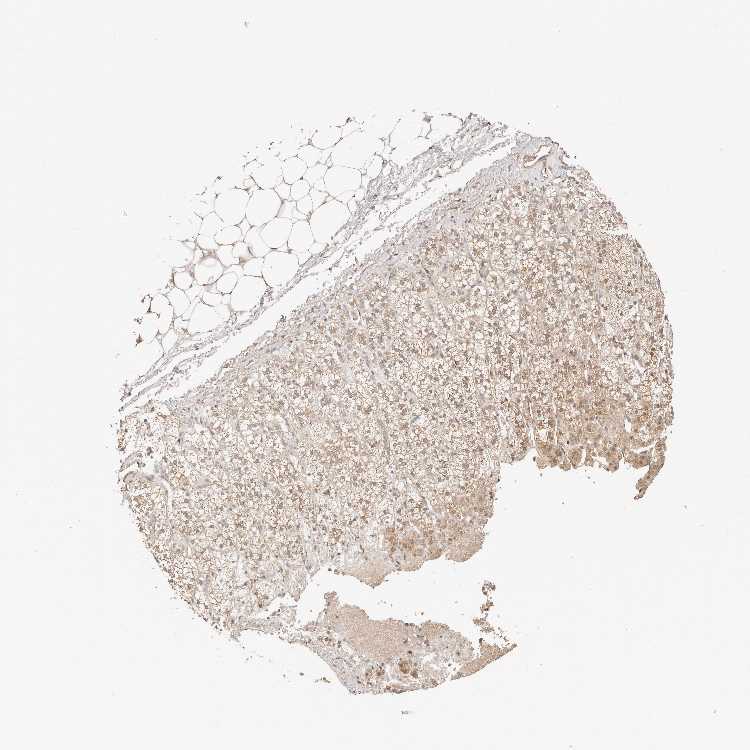

ADRENAL GLAND - Antibody stainingi

Antibody staining in the annotated cell types in the current human tissue is reported as not detected, low, medium, or high, based on conventional immunohistochemistry profiling in selected tissues. This score is based on the combination of the staining intensity and fraction of stained cells.

Each image is clickable and will lead to virtual microscopy that enables deeper exploration of all samples and also displays staining intensity scores, fraction scores and subcellular localization as well as patient and tissue information for each sample.

Antibody HPA030212Antibody HPA030213Antibody HPA030214Antibody HPA030215Antibody CAB013496

Glandular cells MediumLowMediumHighNot detected